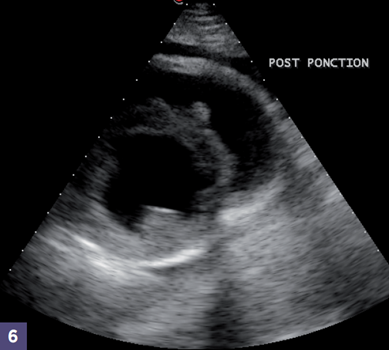

Photo 5 - Fin de la ponction et retrait du cathéter. (Photos 5 & 6)

A la fin de la ponction, la bonne vidange du liquide d’épanchement est contrôlée échographiquement.

La ponction est rarement totale, et une petite quantité de liquide persiste dans l’espace péricardique.

Photo 6